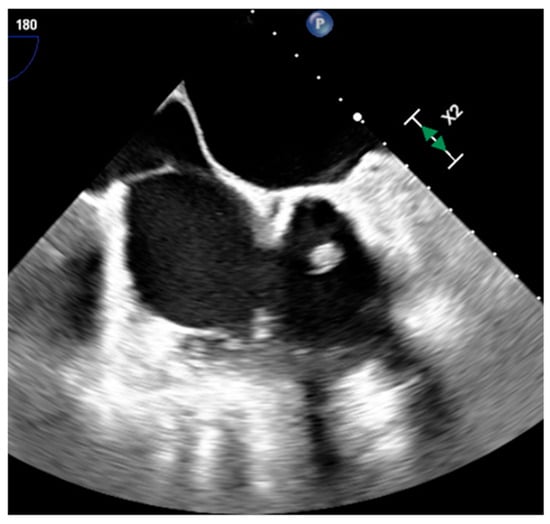

2.2. Lipomatous Hypertrophy of the Inter-Atrial Septum (LHIS or LHAS)

| LHIS | Late adulthood. Obesity | IAS | Usually, asymptomatic. Atrial arrhythmias | mass like deposition of brown fat in the IAS which spares the fossa ovalis | Homogeneous hyperechoic dumbbell appearance of atrial septum | mass with fat-attenuation which spares the fossa ovalis | Hyper T1w and T2w, no LGE, hypo on STIR and other fat-suppression sequences |